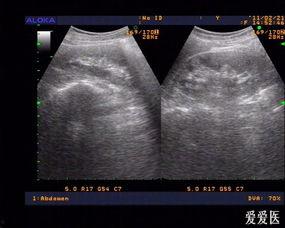

阑尾炎,这个名字听起来就让人心生恐惧。那么,阑尾炎的照片又会是什么样子呢?首先,我们要知道,阑尾炎是一种炎症性疾病,通常发生在人体的阑尾部位。阑尾,这个看似不起眼的小器官,位于人体右下腹,连接着盲肠。

当阑尾发炎时,它的外观会发生一些变化。通过一些医学图片,我们可以看到,阑尾炎的阑尾会变得红肿、增大,甚至可能形成脓肿。这些照片,虽然有些令人不适,但却是医生诊断阑尾炎的重要依据。

那么,阑尾炎的照片中,我们能否看到这些成因的痕迹呢?答案是可以的。在医学照片中,我们可以看到,阑尾炎的阑尾壁会变得增厚,甚至出现脓肿。这些变化,都是细菌感染和炎症反应的结果。